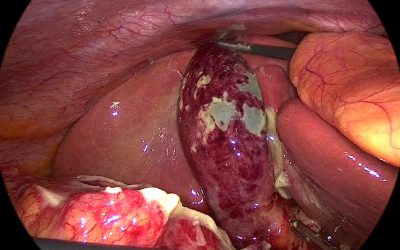

Un caso di tumore benigno della milza: osservazione o splenectomia?

di Enrico Ganz Quale è la migliore strategia per una formazione solida della milza, verosimilmente benigna? Affrontare una questione di questo tipo non è del tutto banale. I tumori splenici benigni sono piuttosto rari e nei testi di Chirurgia poco è speso al...